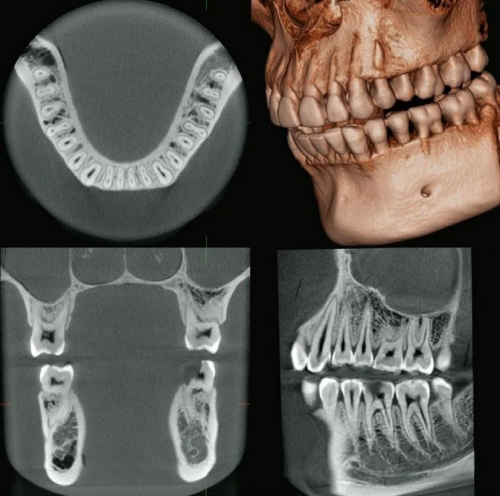

Врачи стоматологической клиники ВГМУ им. Н. Н. Бурденко освоили инновационную методику имплантации Подробнее...